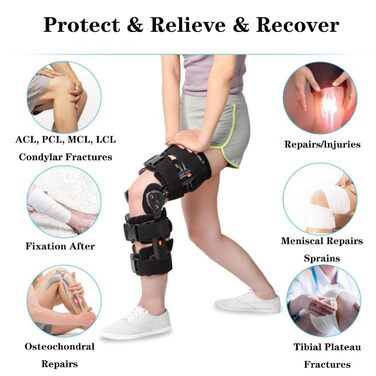

Опис Колінний ортез SFKLYU з шарніром регульований післяопераційний колінний ортез стабілізатор ноги для чоловіків і жінок, ортопедичний захисний ортез, стабілізатор, один розмір, B

- Напіввідкрита конструкція: шарнірний колінний бандаж легкий, але міцний і забезпечує виняткову підтримку. Відкрита конструкція шарнірного наколінника для післяопераційного коліна підходить для правої або лівої ноги, а регульований клейкий ремінь забезпечує комфортну посадку для чоловіків і жінок.

- Легкі та дихаючі: Нековзна підкладка та регульований ремінець з дихаючої тканини гарантують, що вам не буде душно та слизько протягом усього дня. Він не тільки легкий, але й забезпечує сильну, спеціалізовану підтримку. Він забезпечує стійкий ефект відновлення, але не заважає вашій повсякденній діяльності.

- -10-90 регульована фіксуюча ручка: Шарнірний колінний бандаж з регульованою фіксуючою ручкою може контролювати або обмежувати діапазон рухів під час відновлення та реабілітації після операції, щоб запобігти повторному травмуванню. Двосторонні налаштування діапазону рухів можна регулювати в межах -10-110 згинання та -10-90 розгинання, щоб задовольнити конкретні потреби пацієнтів.

- Легко носити: Вам потрібно лише закрити/відкрити пряжку, щоб закінчити надягання та зняття. Після початкового налаштування він дуже простий у використанні. Цей розвантажувальний колінний бандаж універсальний і легко підходить для широкого кола пацієнтів. Його можна використовувати для лівої та правої ноги, а довжина регулюється, тому ви можете змінювати розмір відповідно до свого зросту.

- Застосування: Підходить для відновлення після операції на коліні, травм внутрішніх і зовнішніх зв'язок та задньої хрестоподібної зв'язки або післяопераційного відновлення. Також підходить для розпушування коліна та післяопераційної реабілітації при артриті, переломах тощо.